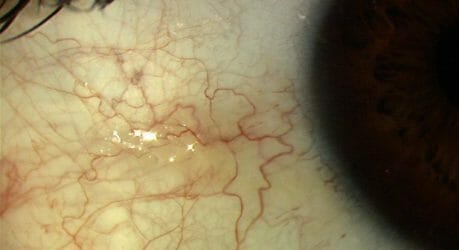

Dry Eye